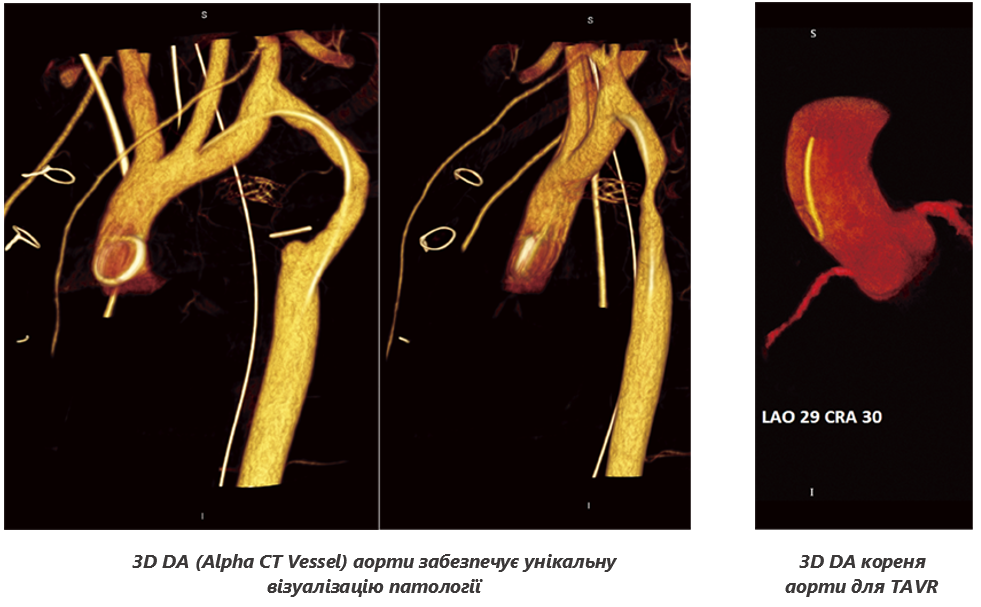

3D DA (Alpha CT Vessel)

Обертання С-дуги у комбінації із високою швидкістю «зйомки» може використовуватися для створення 3D реконструйованих об’ємів анатомії судин. Отриманий 3D-об’єм судин можна обертати в будь-якому напрямку, щоб надати клініцистам додатковий огляд анатомії, та допомогти їм у діагностиці та лікуванні під час інтервенційних процедур. Огляд зображень, отриманих за допомогою 3D-ротаційної візуалізації, дозволяють лікарям візуалізувати різну анатомію судин, таку як ділянки стенозу, відрив аномальної судини, судину, що живить АВМ, та інші патології зі всіх ракурсів.

Лікарі можуть використовувати цю об’ємну візуалізацію судин під час маніпулювання катетером чи іншим пристроєм у судині.